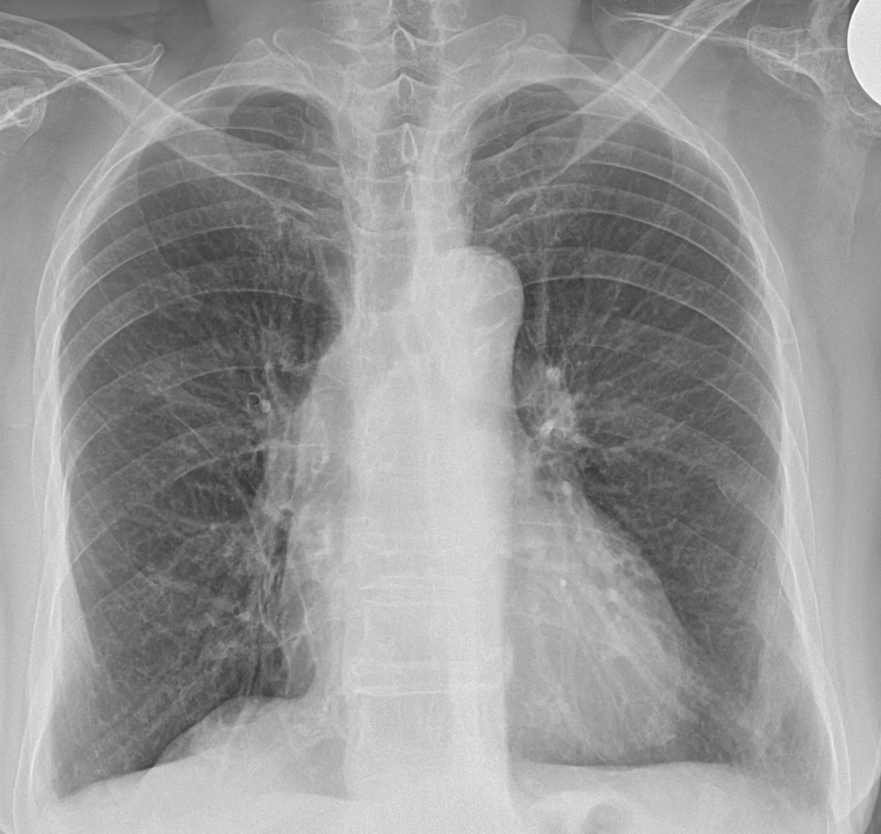

흉막 비후는 흉막이 두꺼워진 것을 말합니다. 보통 흉부 엑스레이나 CT 촬영으로 많이 확인하는 상탭입니다. 흉막은 폐를 둘러싸고 있는 얇은 막으로, 폐가 부드럽게 움직일 수 있게 도와주는 역할을 합니다.

또한, 폐암이 흉막에 퍼질 경우 흉막 비후가 생길 수도 있습니다. 폐암 세포가 흉막을 자극하여 비후가 발생할 수 있는 것입니다. 암이 의심되는 경우, 엑스레이나 CT 촬영을 통해 흉막이 두꺼워진 곳을 더 자세히 검사하게 됩니다.